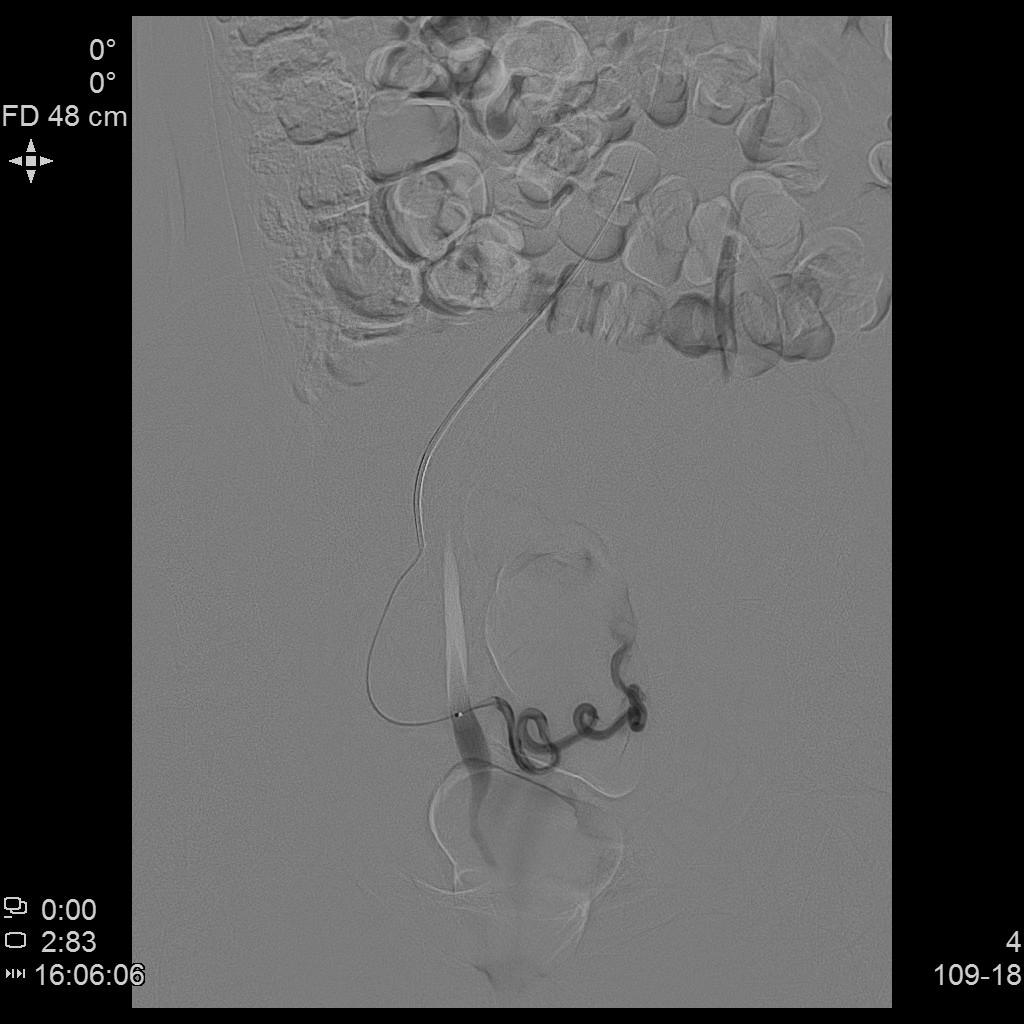

- 经桡动脉入路置入导管造影显示双侧子宫动脉明显增粗,染色丰富,子宫明显增大

- 进一步超选插管右侧子宫动脉造影确认位置

- 微导管进一步超选插管右侧子宫动脉主干造影确认位置